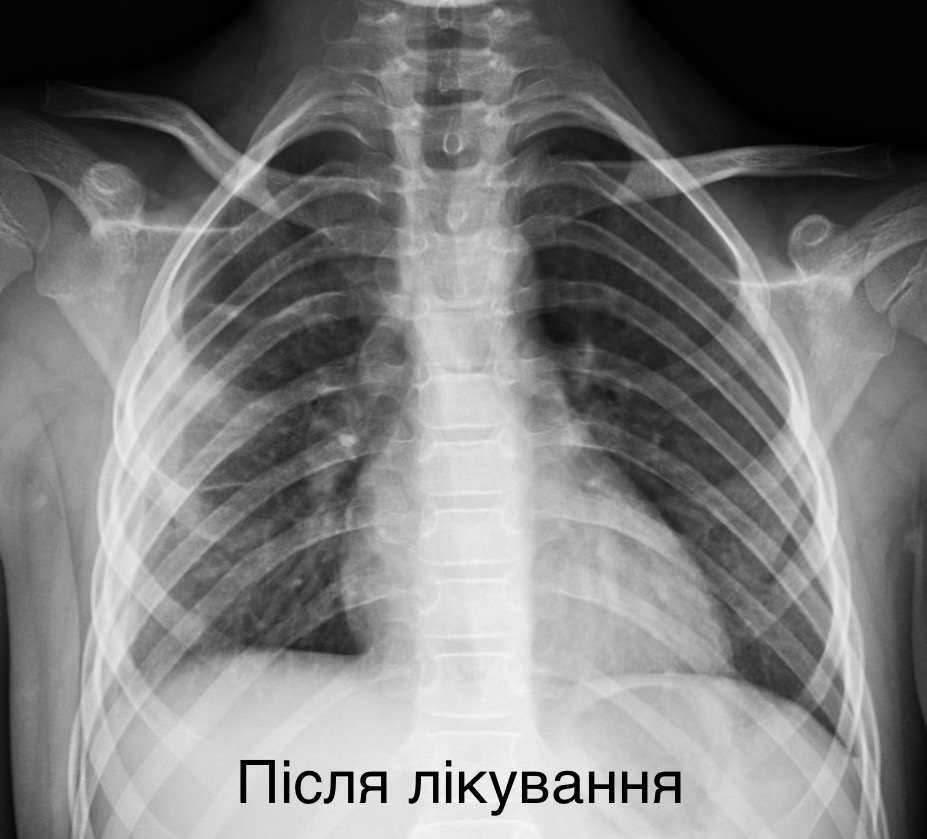

У післяопераційному періоді дівчинка перебувала у відділенні реанімації і знаходилася на апараті ШВЛ.

“Деструктивна пневмонія – одне з найважчих хірургічних захворювань у дітей. Воно стрімко прогресує, загрожує життю, і вимагає не просто досвіду, а чіткої злагодженої роботи всієї команди. Працюють торакальні хірурги, анестезіологи, пульмонологи, реаніматологи, лікарі діагностичного відділення, реабілітологи – усі, щоби повернути дитині можливість жити й дихати”, – коментує керівник Клініки торакальної хірургії та реконструктивної урології у дітей Олег Ленів.

Сьогодні маленька пацієнтка вже не потребує кисню, дихає самостійно, активно відновлюється та усміхається.